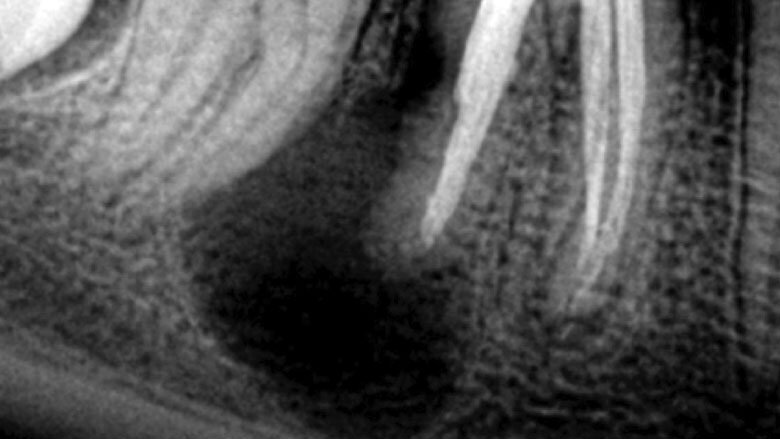

Apicectomía del diente 46.

En ciertas ocasiones, la endodoncia convencional y microcirugía nos muestran limitantes para lograr salvar un diente de la pérdida. Es aquí cuando toma un papel muy importante el reimplante intencional.

El reimplante intencional consiste en extraer el diente de manera atraumática, fuera de boca examinar la causa que produce la infección, y volverlo a reimplantar en el menor tiempo posible.

El reimplante intencional consiste en extraer el diente de manera atraumática, y entonces fuera de boca examinar la causa que produce la infección, y volverlo a reimplantar en el menor tiempo posible.

Se debe proteger al máximo la integridad de las células del ligamento periodontal, para que se dé una buena cicatrización de las mismas durante la reimplantación. La manera de protegerlas es usar un tiempo extraoral extra corto, no mayor a 15 minutos y entre más bajo mejor. Después de la extracción del diente, las raíces se examinan en busca de fracturas, conductos adicionales o istmo y cualquier característica anatómica adicional que requiera sellarse para evitar la salida de bacterias al exterior. La inspección de la raíz se realiza mejor con la ayuda de un microscopio dental6. Dado que no se necesita una osteotomía, la reimplantación no produce la pérdida de hueso vestibular o palatino para llegar al ápice radicular. Esto facilita la curación postoperatoria al no sacrificar hueso sano para llegar al sitio donde se ubica el ápice radicular. Durante la apicectomía convencional, el campo de visión está limitado por la osteotomía y las estructuras adyacentes, como el arco cigomático y el tejido de la mejilla. Sostener un diente extraído permite un acceso total para inspeccionar toda la superficie de la raíz (4). La manipulación de instrumentos microquirúrgicos y ultrasonidos es más fácil con el diente fuera de la boca. Una reducción del tiempo extra oral es imprescindible en la prevención de la anquilosis, la reabsorción radicular y para promover el proceso de curación peri-radicular mediante la prevención del daño y deshidratación de las células periodontales7. Es grandioso darse cuenta cómo los pacientes quedan altamente agradecidos por conservar sus dientes. Es el endodoncista o el odontólogo el que decide desahuciar dientes que pueden salvarse, y si como especialistas nos entrenamos en técnicas avanzadas, más dientes podremos salvar de la pérdida. En muchos casos, factores económicos impiden que un paciente que pierde los dientes, pueda reemplazarlos, y la falta de dientes está relacionado con problemas gastrointestinales, con cáncer de estomago, cáncer colon rectal e inclusive con Alzheimer8.9. Debemos de verdad aumentar el valor que le damos a los dientes naturales; si fuéramos a perder un riñón, ¿no agotaríamos todos los recursos por salvarlo? Nuestra meta debe ser lograr que nuestros pacientes lleguen con sus dientes naturales hasta la vejez.